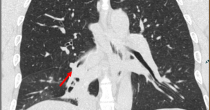

PET/CT图:右肺下叶支气管根部结节,FDG代谢增高

结果派特CT影像表现:右肺下叶支气管根部软组织密度结节影,直径约17mm,管腔明显狭窄,FDG摄取增高,SUVmax=3.29;右肺下叶基底段支气管狭窄,并见不规则形实变,内见支气管扩张、充气,FDG轻度摄取,SUVmax=2.18。

影像表现:右肺下叶支气管根部软组织密度结节影,直径约17mm,管腔明显狭窄,FDG摄取增高,SUVmax=3.29;右肺下叶基底段支气管狭窄,并见不规则形实变,内见支气管扩张、充气,FDG轻度摄取,SUVmax=2.18。

印象:右肺下叶支气管根部肿物,FDG代谢增高,考虑肺癌,继发性右肺下叶阻塞性肺不张及阻塞性肺炎。后行支气管镜检查。病理结果为:支气管根部肺癌(黏液表皮样癌)。